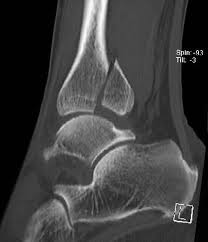

Eine Sprunggelenksfraktur wird durch die Klassifikation nach Weber aufgrund der Frakturhöhe am Wadenbein Außenknöchel in drei verschiedene Formen unterteilt. Bist du operiert worden. Häufig ist bei diesem Knöchelbruch am Wadenbein die Syndesmose verletzt und die Stabilität der Sprunggelenksgabel nicht mehr gewährleistet.

Ich habe mir im Mai eine Weber B Stressfraktur zugezogen die zuerst übersehen und erst Mitte Juni mit einem vierwöchigen Vakoped versorgt wurde. Außenknöchelfraktur unterhalb der Syndesmose Syndesmose immer intakt Weber B. Mein Erfahrungsbericht zur Behandlung Operation und Heilungsverlauf nach einem Sprunggelenkbruch.